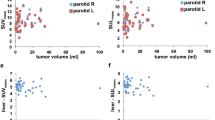

Despite the visually appreciable similarities, there were subtle but statistically significant differences in the quantitative analysis of normal-organ uptake amidst the two agents. Detailed comparison is described in Table 2 and depicted in Figs. 3 and 4. Liver tracer quantification between tracers was well correlated, allowing for some variability on a per-patient basis (Fig. 3d). Quantitative uptake was slightly higher in 18F-DCFPyL scans (mean SUVpeak 7.5 vs 6.7, p = 0.001), associating with a mean bias of 0.79 ± 1.30 (Fig. 4d). In contrast, the spleen presented significantly higher 68Ga-PSMA-11 uptake values (median SUVpeak 9.4 vs 4.9, p < 0.001). While splenic activity quantification also correlated well (Fig. 3e), there was an increasing proportional bias at higher uptake values (Fig. 4e, r = 0.681, p < 0.001, mean bias − 4.49 ± 1.78). Tracer activity in the renal cortex was also significantly higher in 68Ga-PSMA-11 scans (mean SUVpeak 59.6 vs 40.0, p < 0.001), with a mean bias of − 19.60 ± 9.52 (Fig. 4g). Lacrimal and major salivary glands had a good correlation in quantitative uptake between the two scans (Fig. 3a, b, c) and an acceptable overall agreement with a calculated mean bias of − 0.39 ± 1.49 in lacrimal, − 2.08 ± 2.39 in parotid, and − 3.21 ± 2.46 in submandibular glands (Fig. 4a, b, c).

Scatter Plotts depicting the relation of quantitative uptake values (SUVpeak) between the two scans in each of the target organs (y axis: 18F-DCFPyL SUVpeak; x axis: 68Ga-PSMA-11-SUVpeak). Statistically significant correlations (p < 0.01) show the corresponding regression lines and 95% CI for the slope

Bland-Altman Plotts showing the differences between quantitative uptake values (ΔSUVpeak, determined by 18F-DCFPyL SUVpeak – [minus] 68Ga-PSMA-11-SUVpeak) between the two scans (y axis) against their average - Average SUVpeak (x axis). Plotted dotted lines represent the mean Bias in the entire cohort and 95% limits of agreement